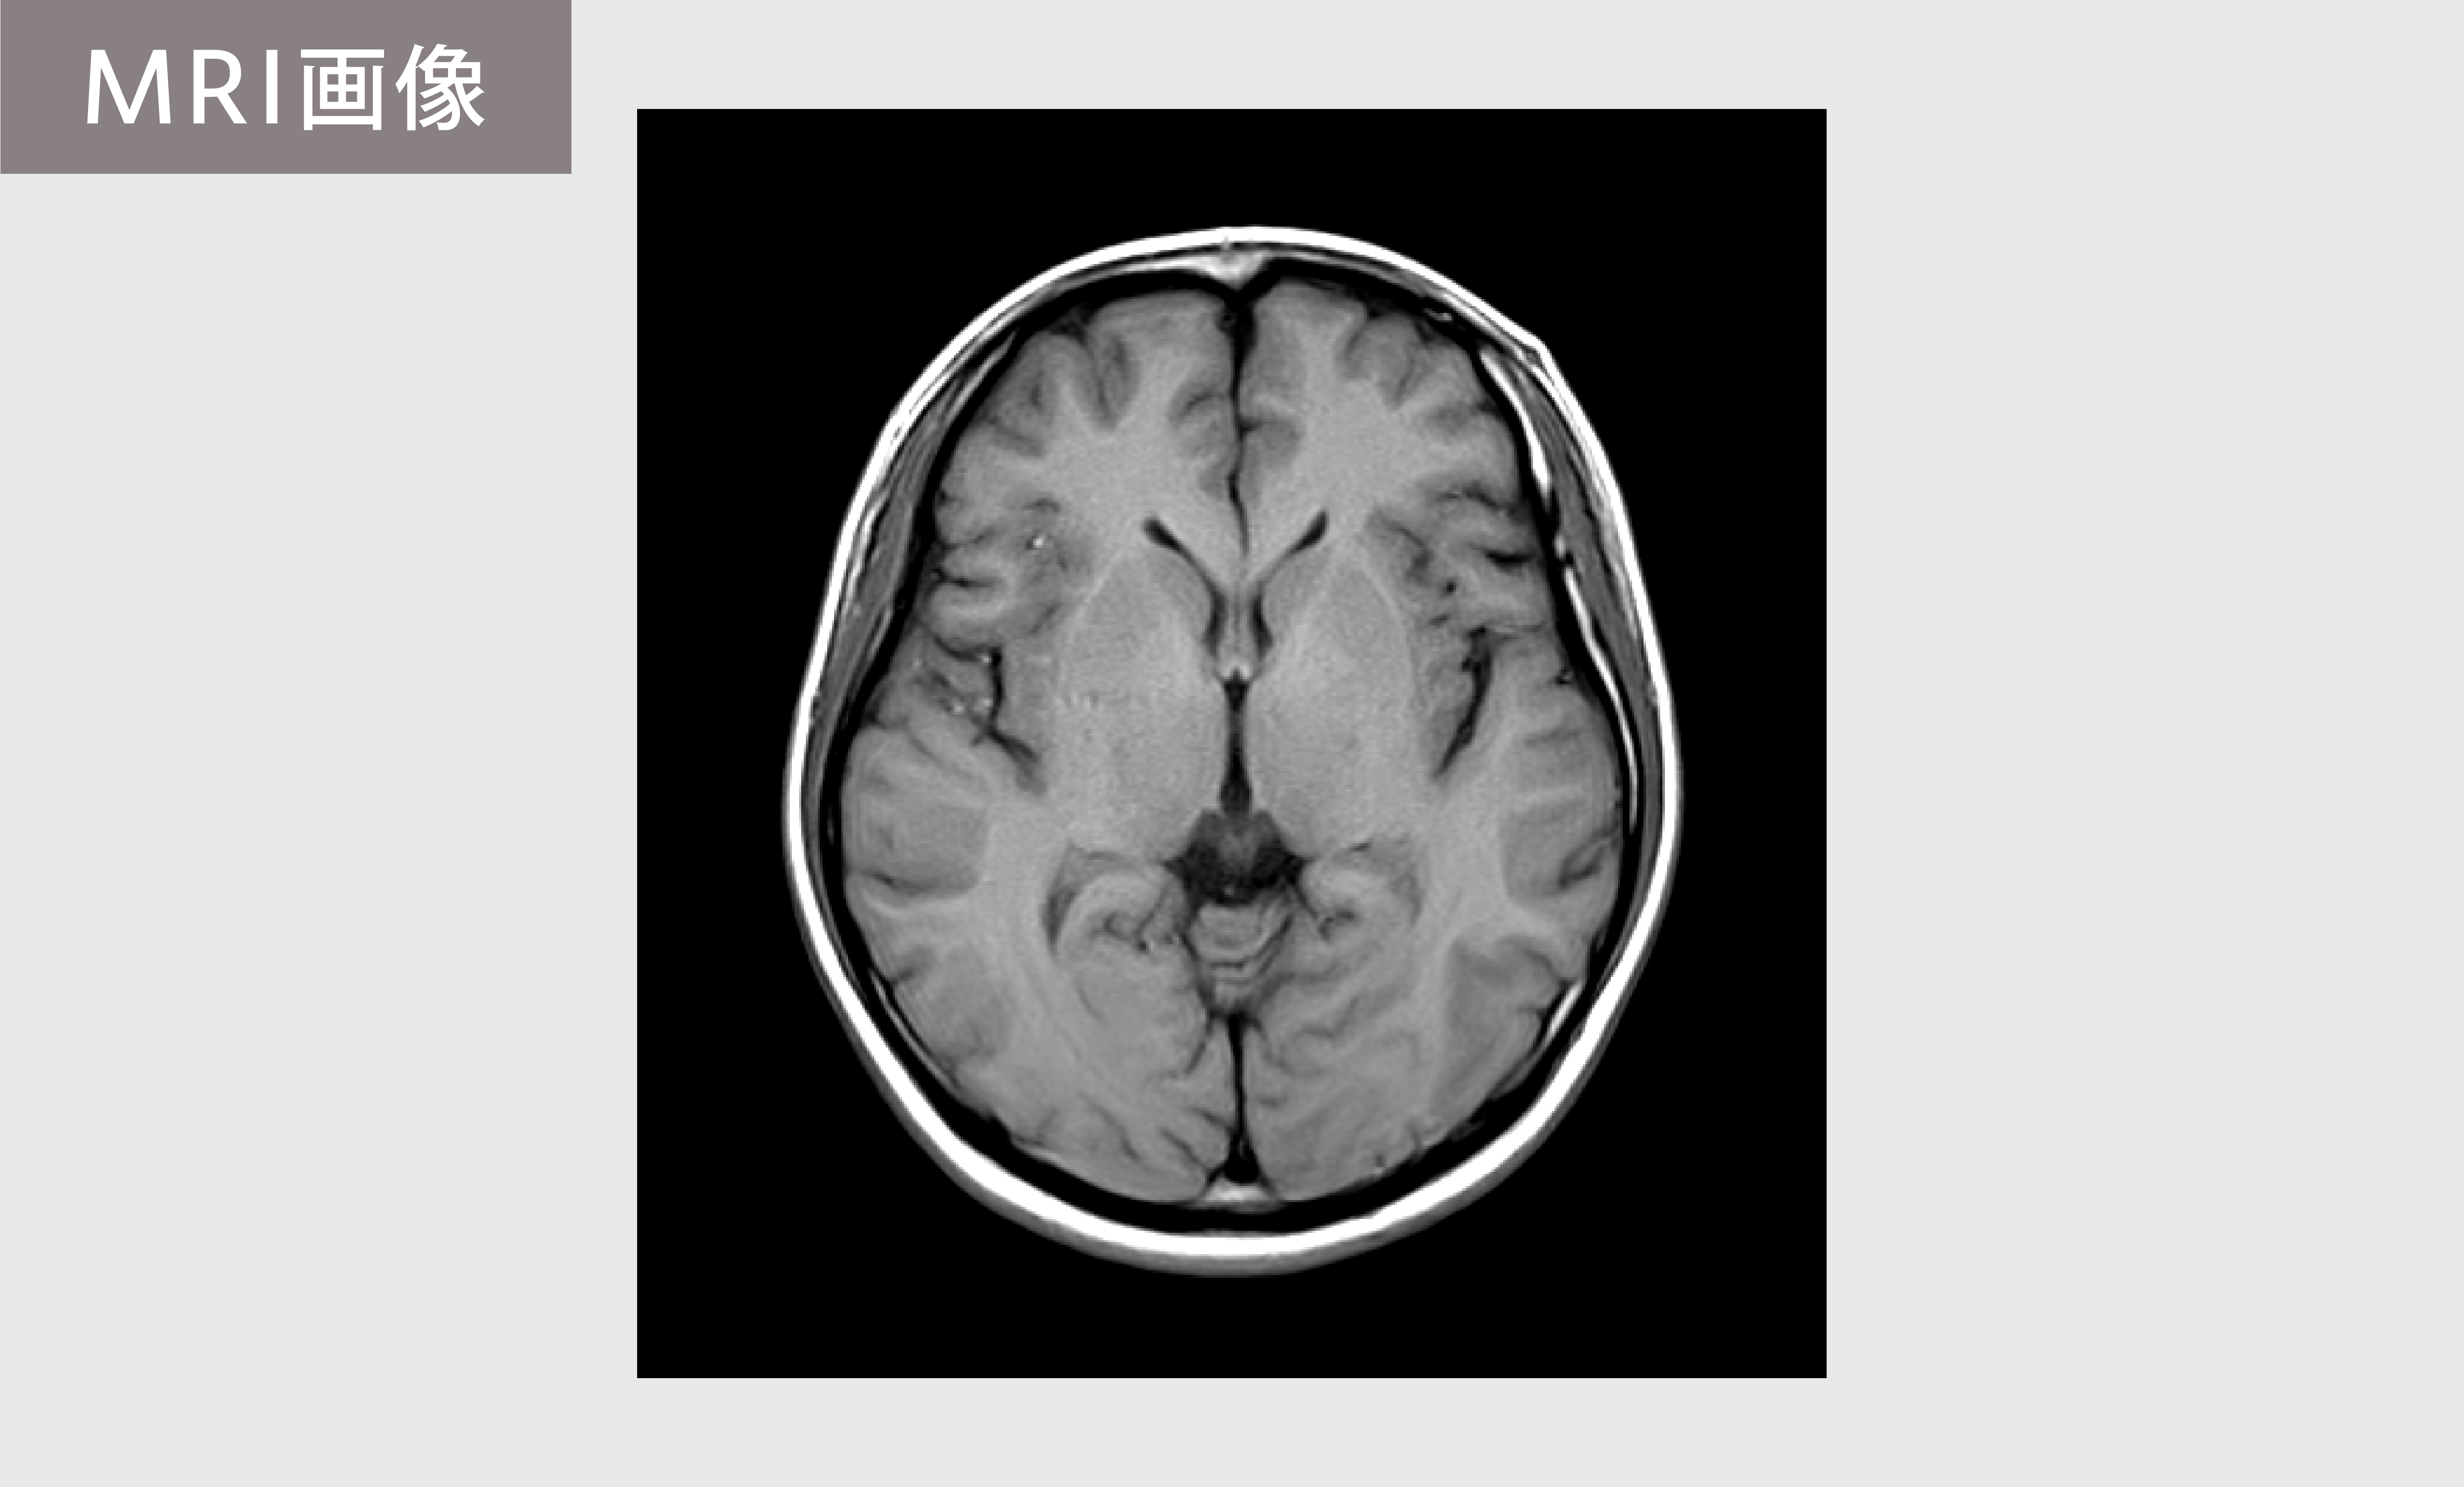

MRI(Magnetic Resonance Image:磁気共鳴画像)は、強い磁石と電磁波を使って、体の内部の詳細な断層画像を撮影する検査です。

放射線は使用しないため、被ばくのおそれがありません。

MRIは骨の影響を受けないため、脳の深部まで細部を確認でき、わずかな異常も発見しやすい特徴があります。

さらに、血管の状態を詳しく調べるMRA(磁気共鳴血管撮影)も同時に行い、脳動脈瘤、血管の狭窄・閉塞など、重大な病気につながる異常を確認できます。